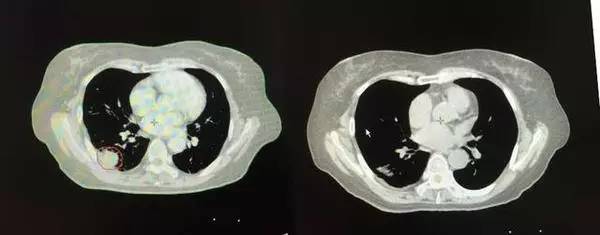

右肺病灶

2013年治疗前 治疗后

左肺病灶

2013年 2015年完全消失

13年7月20日被诊断为小细胞肺癌,并伴纵膈淋巴结多处转移,胸水。经A45治疗,患者原发病灶和转移病灶基本消失。左两图为肿瘤治疗前的CT、 PET-CT图像,右两图为治疗后图像,原发病灶和淋巴结转移病灶基本消失,胸水消退,目前患者生活质量良好。

左两图为肿瘤治疗前的CT、 PET-CT图像,右两图为治疗后图像,原发病灶和淋巴结转移病灶基本消失,胸水消退,目前患者生活质量良好。